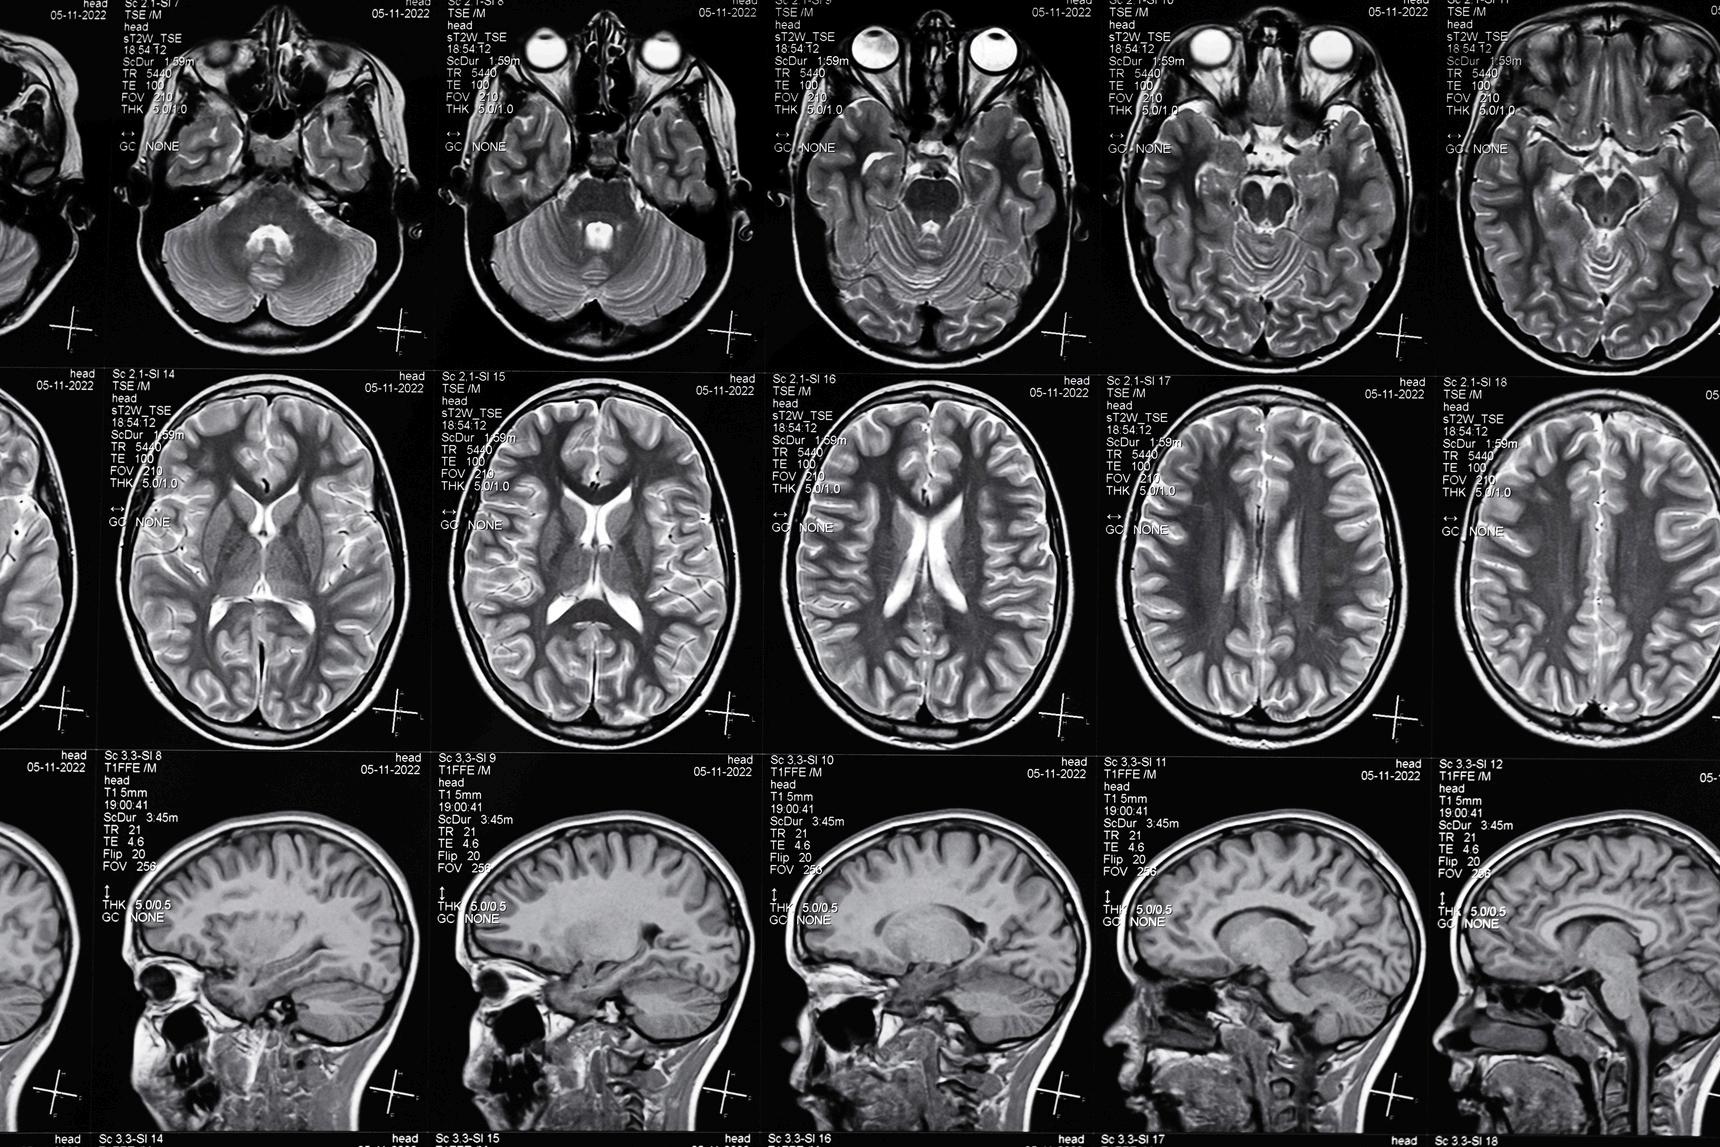

Sabato Santaniello (BME) has a background in Computer Science Engineering from his undergraduate studies and a graduate degree in BME with a focus on Systems and Control Theory. In the beginning of his graduate school career, Sabato hypothesized that “Systems and Control Theory could have a huge impact in improving the design of interventions that may restore important functions in impaired subjects ” This hypothesis led him to apply his ideas to the treatment of motor symptoms in Parkinson’s Disease and Essential Tremors At UConn, Sabato helped to improve the engineering aspects of deep brain stimulation (DBS) for Parkinson’s Disease with the goal in mind of making DBS “truly amenable for larger populations ” A current project focuses on using cerebellar transcranial magnetic stimulation (TMS) to control tremors in patients with Essential Tremor Cerebellar TMS is a challenging procedure to perform, however Sabato’s Lab has been working on a software that recreates a 3D image of the cerebellum from an MRI scan, creating a “virtual cerebellum.” With this software, Sabato says “we can now study in simulation how TMS pulses would affect neural oscillations in the cerebellum, which are reliable biomarkers of the tremor and test out the safety and efficacy of new TMS pulses ” Sabato has also recently started a collaboration with colleagues in PNB (Dr. Rich), UConn Health (Dr Conner), and other institutions outside of Connecticut, to investigate the activity of sensory and motor cortices in patients with Parkinson’s Disease When discussing this research Sabato explains, “the idea is to find biomarkers in the cortical field potentials that may help us decide which contact on the deep brain stimulation electrode lead should be activated and what stimulation setting should be used to maximize the therapeutic outcomes ” Sabato and his collaborators hope to better understand the neural underpinnings of these traits and refine algorithms to detect and use these trains for optimizing the therapeutic response to deep brain stimulation In addition to his research, Sabato teaches technical courses that introduce BME students to principles of modeling, machine learning, and signal processing. Sabato likes to use active learning paradigms incorporating certain topics, software, or tools that are the core of his research, and the greatest benefit and intellectual satisfaction to his students “always comes from applying new methods or software presented in class to actual